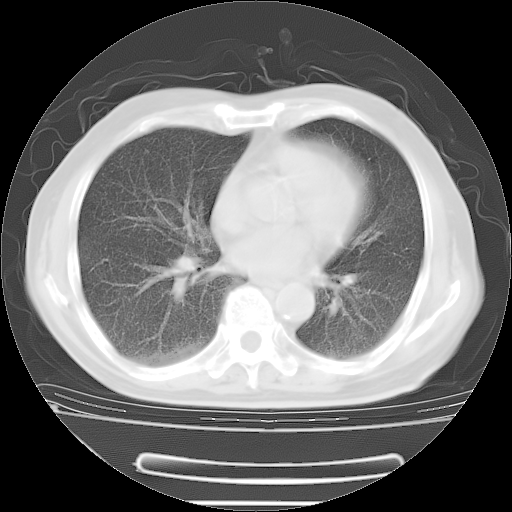

今天复查肺部CT,发现双肺广泛磨玻璃样改变。所以我把3月19日和5月9日相隔50天的肺部CT上传。请大家会诊。

2009年3月19日肺部CT片。

5月9日肺部CT(在4月27日齐鲁医院肺部CT描述部分肺组织磨玻璃样改变,12天后肺组织广泛磨玻璃样改变)

大致读了系列胸部CT:纵隔窗无明显异常,肺窗:从4、27至今:主要是双肺中下野外带可见毛玻璃样改变,目前处于急性肺泡炎阶段,至于原因考虑1、结替组织或胶原血管性疾病所致?2、恶性疾病如恶组在肺部所致的表现或细支气管肺泡癌?3、药物或其它原因如肺蛋白沉着症所致肺泡炎目前不太可能?总之,明天就去请我院的呼吸科、感染科、血液科和临免专家会诊哈。